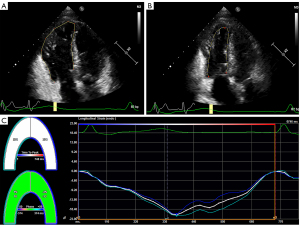

The 2D-STE analysis was performed in the RV-focused apical four-chamber view. Locating points were respectively placed on the endocardium of the RV free wall side and the interventricular septum side of the tricuspid annulus and the RV apex (Figure 1A,1B). Subsequently, software was used to automatically segment the RV into six segments (basal, middle, and apical segments of both the RV free wall and the interventricular septum) and track the myocardial speckle motion throughout the cardiac cycle. The endocardial boundary was manually modified by the operator if the tracking was insufficient. Finally, RV longitudinal strain curves of the free wall and septum were automatically generated by the software (Figure 1C). Two-dimensional RV free wall longitudinal strain (2D-RVFWLS) was calculated as the average value of the longitudinal strain of the basal, middle, and apical segments of the RV free wall. After exclusion of 6 patients who were lost to follow-up, 24 out of 30 patients underwent 2D-STE analysis. Manual adjustments of the endocardial boundaries were made in the 10 patients with poor image quality. After the adjustment, 1 patient was still excluded due to the image quality being too poor for 2D-STE analysis. Therefore, the feasibility rate of 2D-STE analysis in patients with repaired TOF in terms of suboptimal windows and subsequent need for manual adjustments was 90%.